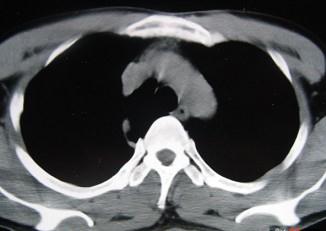

男,40岁,CT检查如图,最可能的诊断为 ( )A、右上肺占位B、右上肺奇叶形成C、右上肺陈旧性结核灶D、右上肺不张E、右上肺纤维化

问题 男,40岁,CT检查如图,最可能的诊断为 ( )

选项 A、右上肺占位 B、右上肺奇叶形成 C、右上肺陈旧性结核灶 D、右上肺不张 E、右上肺纤维化

答案 B